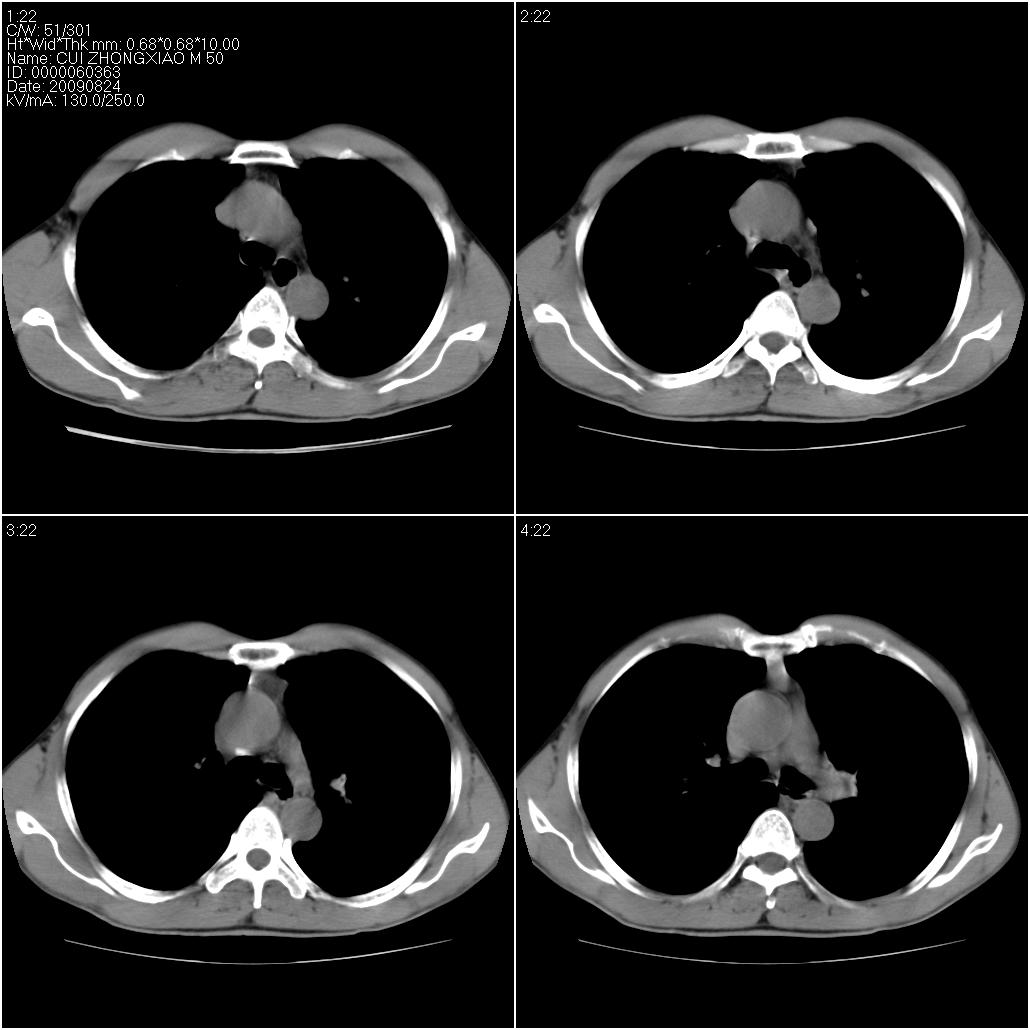

标题: CT21851:男性,50岁。间断性咳嗽半年。 [打印本页]

标题: CT21851:男性,50岁。间断性咳嗽半年。

磨玻璃样改变(左肺及右肺上叶前段),边缘模糊,考虑炎症,建议严格抗炎治疗后复查除外肺泡蛋白沉积症或肺泡出血(病人有咯血吗) 肺泡癌.

肝左叶肝内胆管扩张,进一步检查.